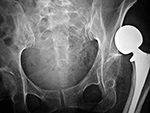

| Dislocated total hip arthroplasty |

Elderly woman with bilateral press fit total hip arthroplasties. There is a dislocation on the right. |